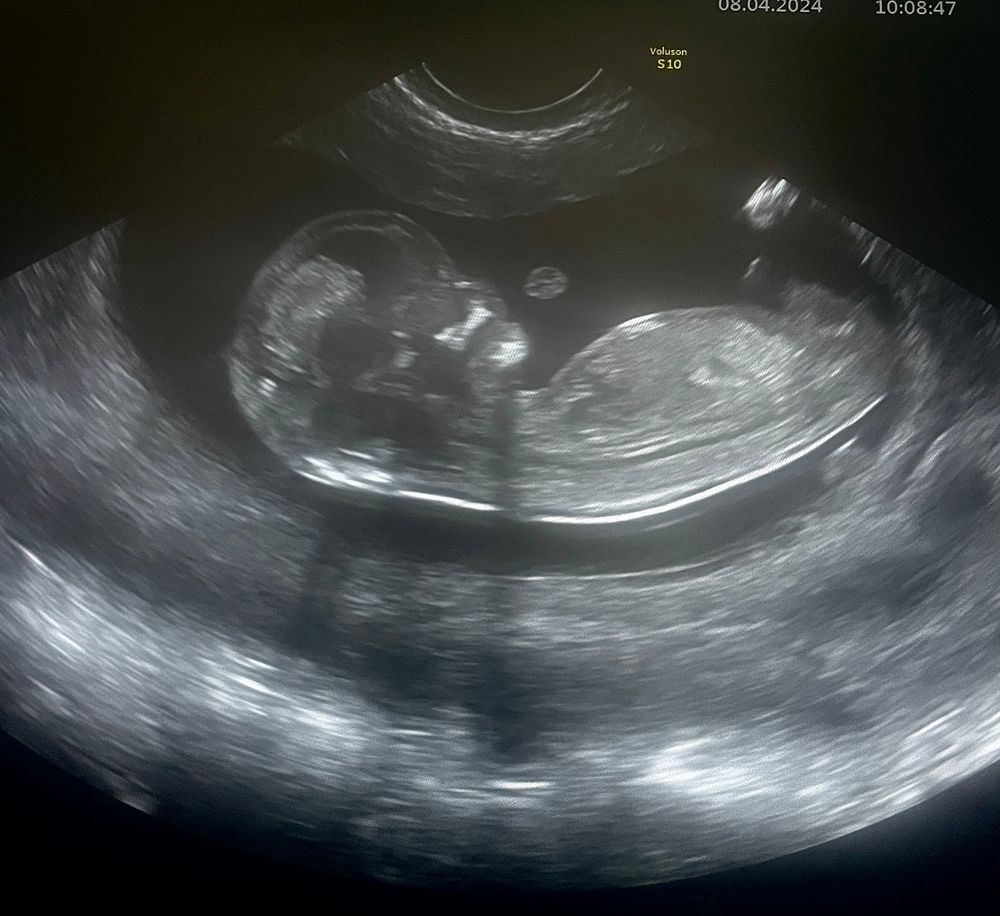

А креветка то уже совсем не креветка, а вполне себе уже человечек😄🥰

срок по мес - 11.3, срок по УЗИ - 11.5

КТР 50, сердцебиение 154, ТВП 1,5, нос 2,5

сказали все хорошо)) осталось дождаться результатов крови. Отслойки уже нет. Пол не предположили. Что-то там болталось между ног, но сказали это у всех так болтается и ни о чем не говорит))